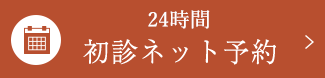

初診時の口腔内

上顎(写真:左)は、一見分かりにくいですが多量の歯肉縁下歯石、下顎(写真:右)は歯肉縁上歯石、縁下歯石が沈着。歯肉の炎症が強く、触るとすぐに出血する状態でした。患者様ご自身はブラッシング時に時々出血はするものの、特に痛みもなく、大きな自覚症状はないとのことでした。しかし、細菌検査では、基準値の10倍近い細菌数を検出しました。